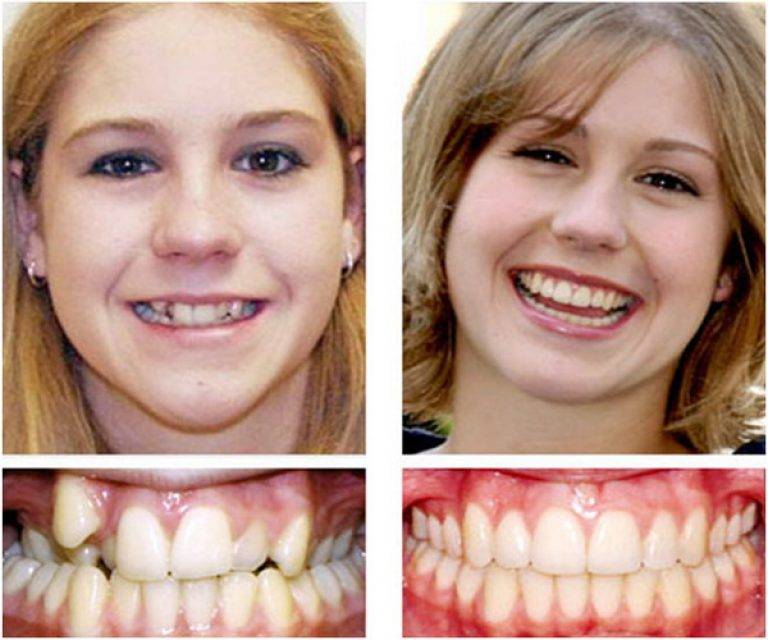

Исправление прикуса брекетами

Это самый популярный метод коррекции прикуса, который эффективный и для детей, и для взрослых. Брекеты — это система, состоящая из замочков и дуги. Замочки приклеиваются к зубам специальным клеем и в них продевается дуга, которая давит на зубы и возвращает их в нужное положение.

Брекеты позволяют справиться почти с любыми аномалиями прикуса, вне зависимости от состояния зубов и возраста пациента. Единственное отличие заключается в том, что с возрастом длительность лечения увеличивается. Если у ребенка и подростка исправление даже самой сложной аномалии прикуса занимает до года, то у взрослого оно может растянуться до двух-трех лет из-за того, что кости уже плотные, а челюсть сформирована.

Результат до и после ношения брекетов